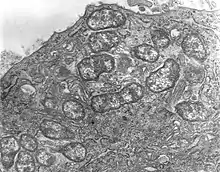

| Orientia tsutsugamushi | |

Orientia is a genus of bacteria in family Rickettsiaceae. They are obligate intracellular, gram-negative bacteria found in insects and mammals. They are spread through the bites or feces of infected insects.